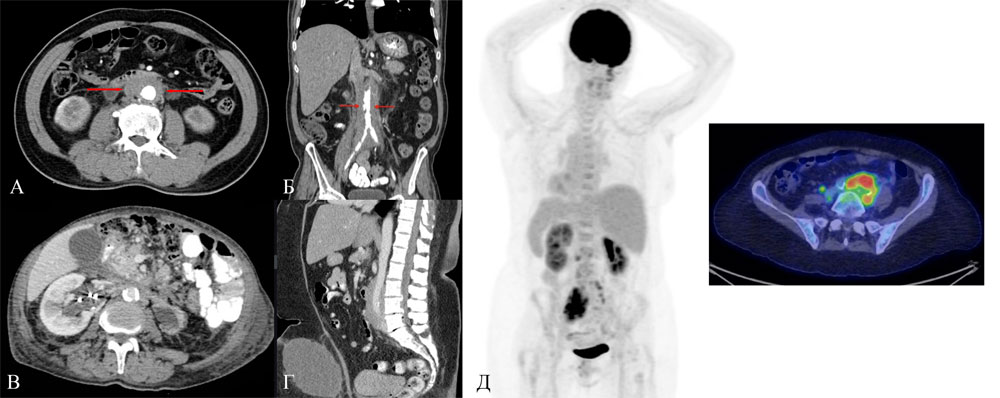

Еще одним примером иммобилизации, служит болезнь Ормонда (идиопатический ретроперитонеальный фиброз). Вследствие активного разрастания фиброзной ткани происходит выраженное сдавление и фиксация анатомических структур в забрюшинном пространстве. Патогенез заболевания, хотя и до конца не изучен, часто связывают с аутоиммунными механизмами, при которых хроническое воспаление, опосредованное лимфоцитами и макрофагами, приводит к избыточному отложению коллагена и образованию плотной соединительной ткани. Этот фиброзный конгломерат формирует жесткий футляр, который механически иммобилизует, инкапсулирует и сдавливает критически важные структуры, прежде всего мочеточники, что клинически проявляется нарушением оттока мочи и развитием гидронефроза. Помимо мочеточников, объектом иммобилизации могут становиться нижняя полая вена (провоцируя отеки нижних конечностей), брюшная аорта (с риском ишемии) и нервные сплетения, что в совокупности приводит к полиорганной дисфункции. Болезнь Ормонда является наглядным примером того, как неконтролируемый процесс фиброгенеза выполняет роль биологического «цемента», патологически обездвиживая органы и нарушая их физиологическую функцию (рисунок 7).

![Рисунок 7. Ретроперитонеальный фиброз. А-Г — компьютерная томография. Д — позитронная эмиссионная томография с фтордезоксиглюкозой (ФДГ): отмечается высокая ФДГ-авидность активного ретроперитонеального фиброза [23]](/etc/2025/pic9848.jpg)

Рисунок 7. Ретроперитонеальный фиброз. А-Г — компьютерная томография. Д — позитронная эмиссионная томография с фтордезоксиглюкозой (ФДГ): отмечается высокая ФДГ-авидность активного ретроперитонеального фиброза [23]